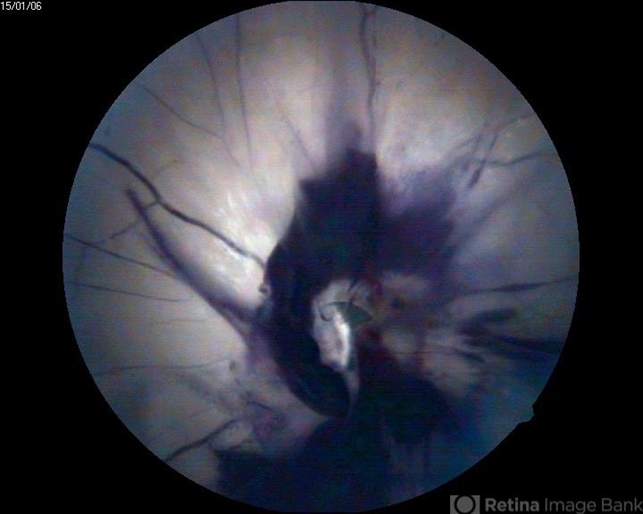

- optic nerve head avulsion

- A 30-year-old male presented with loss of vision following blunt trauma.